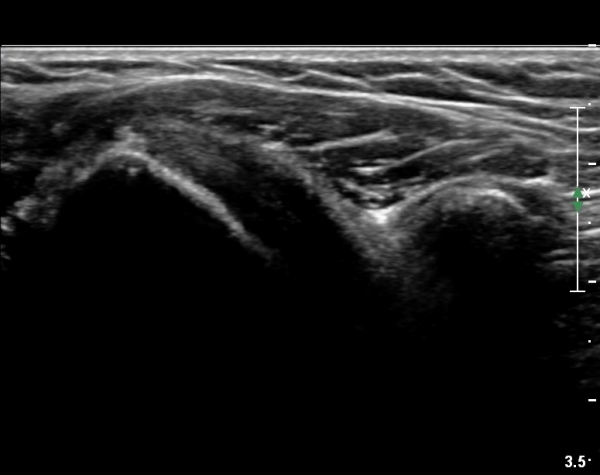

ÃÊÀ½ÆÄ ¼Ò°ß :  ±Ø»ó°Ç Á¾´Ü¸é°Ë»ç¿Í Ⱦ´Ü¸é°Ë»ç»ó ƯÀÌ ¼Ò°ß º¸ÀÌÁö ¾ÊÀ½(»çÁø 1, 2).